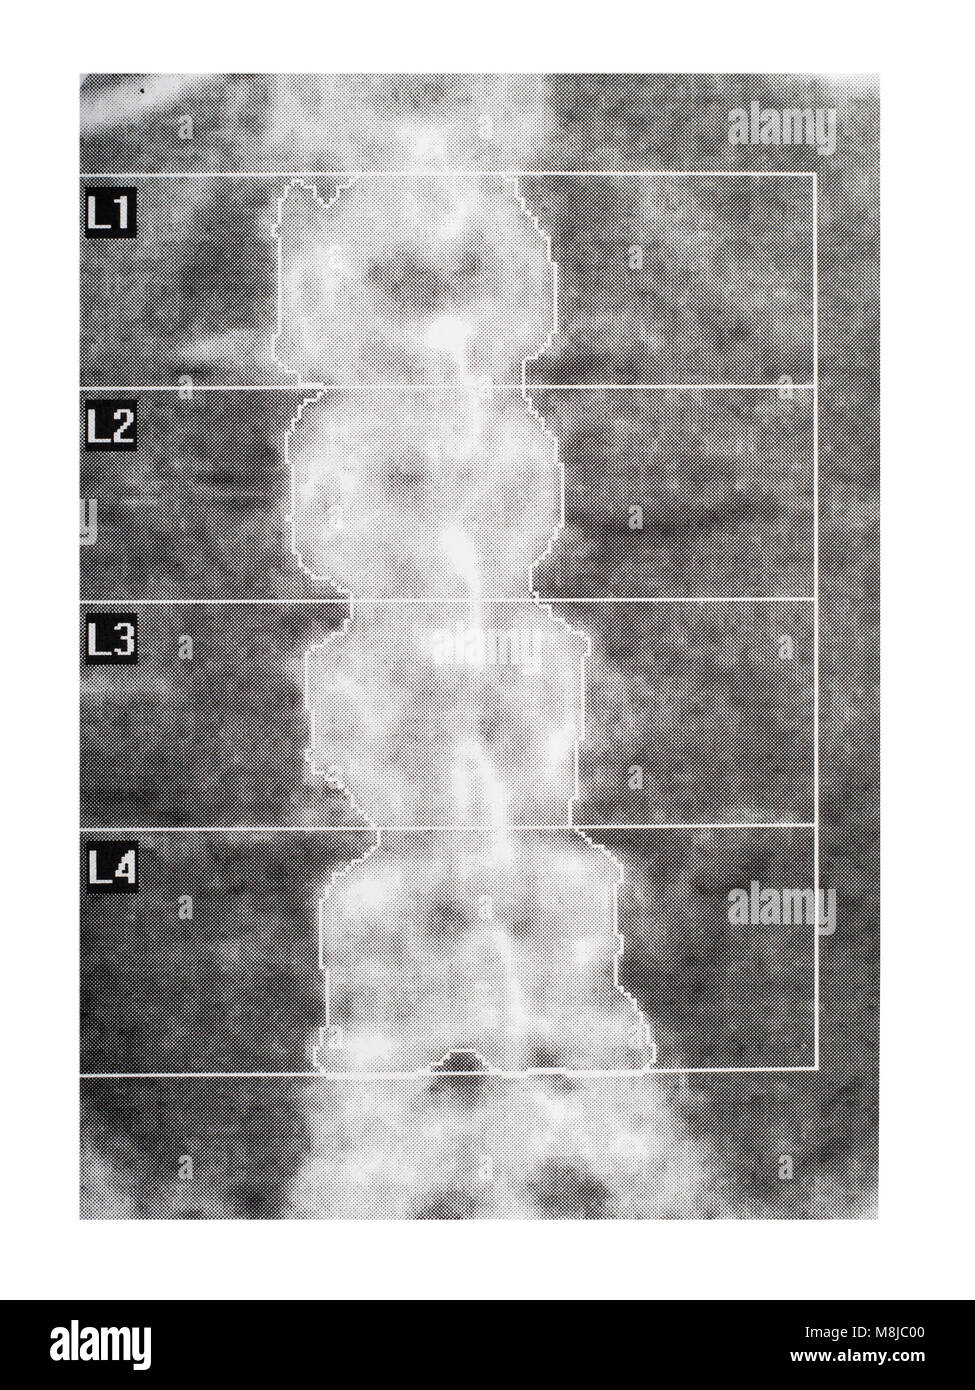

Medical scan - spine. DEXA scan for osteoporosis. Stock Photohttps://www.alamy.com/image-license-details/?v=1https://www.alamy.com/stock-photo-medical-scan-spine-dexa-scan-for-osteoporosis-177425472.html

Medical scan - spine. DEXA scan for osteoporosis. Stock Photohttps://www.alamy.com/image-license-details/?v=1https://www.alamy.com/stock-photo-medical-scan-spine-dexa-scan-for-osteoporosis-177425472.htmlRFM8JC00–Medical scan - spine. DEXA scan for osteoporosis.